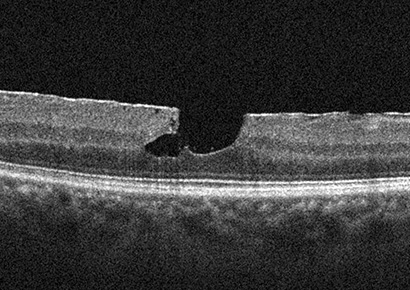

정밀안저검사 및 빛간섭단층촬영 등을 통해 망막 위에 덮인 막의 크기와 두께, 망막의 구조 변화를 정밀하게 확인합니다.

수술 전